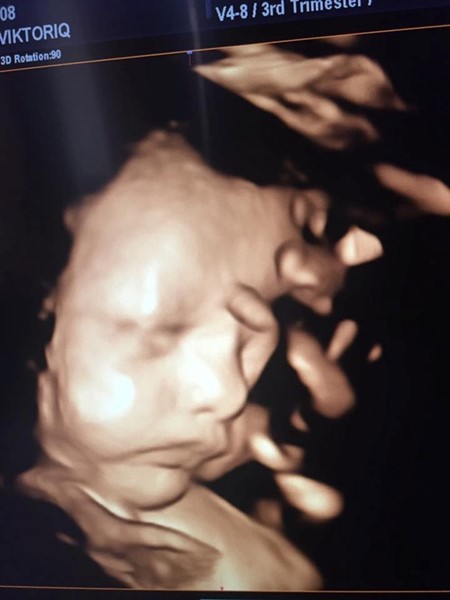

Радослав и Виктория твърдят, че основната вина за смъртта има д-р Георги Георгиев от АГ болницата във Варна, защото неглижирал състоянието на бременната жена и определил изтичането на околоплодните й води като "напикаване". Драмата се разиграла между 28 и 31 август, когато окончателно стана ясно, че плодът е мъртъв.

Според семейството водите на жената са изтекли, плацентата се е отлепила и това е довело до задушаването на детето. Лекарят обаче отвърна, че не чувства вина и съвестта му е чиста, защото "не съм проявил нехайство, немарливост или нежелание да се занимавам със случая".